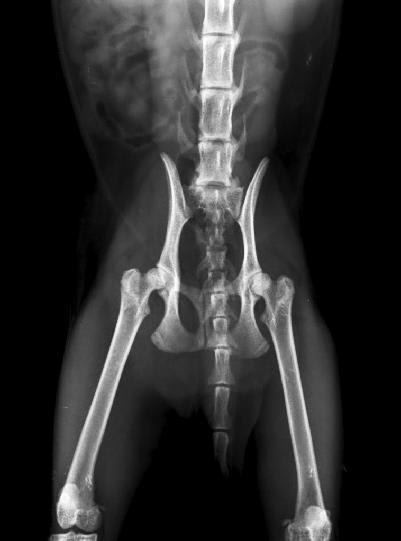

My kitten is one year old, she has calicivirus and has been diagnosed with osteoarthritis. These are hers x-rays. My vet doesn't want to operate. I don't know what to do. Sorry for my grammar mistakes, I am not native english.

Hello, sorry to hear about Kairi. It sounds like besides her calicivirus, she is having some difficult time walking? If so, it is believed that this is secondary to osteoarthritis. Young cats with osteoarthritis can often have more than one joint affected and is often something that is management medically. Finding the underlying cause for this osteoarthritis such as infection, an inflammatory response, auto-immune disease, or an old injury must be determined. Surgery may not be able to treat the osteoarthritis but rather help her walk easier. Surgical intervention is often pursued as a salvage procedure and not before diagnosing the source of the osteoarthritis and its effect. I would recommend asking your veterinarian to refer Kairi to an orthopedic surgeon so that they may evaluate her and determine if one or more joints are affected and if surgery or medical management is best for her. Hope this helps and best of luck.